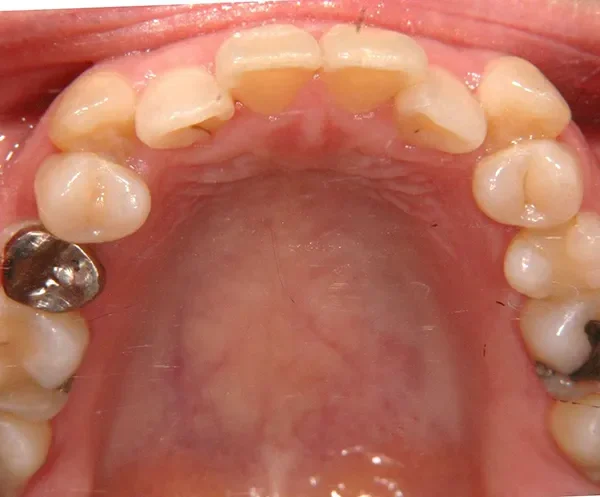

初診時年齢 40歳以上 (女性) 主訴 上下のがたがた・噛み合わない

診断名 叢生 装置名

特徴 ゆがんで生えている

状態 ガタガタ・でこぼこに生えている(叢生)

八重歯(叢生)

上下のがたがたと噛み合わない事を主訴に来院されました。

初診